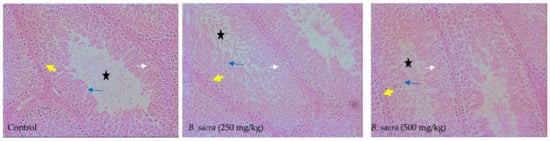

2.2. Effect on Testes in Rats

4.5.2. Testis Parameters